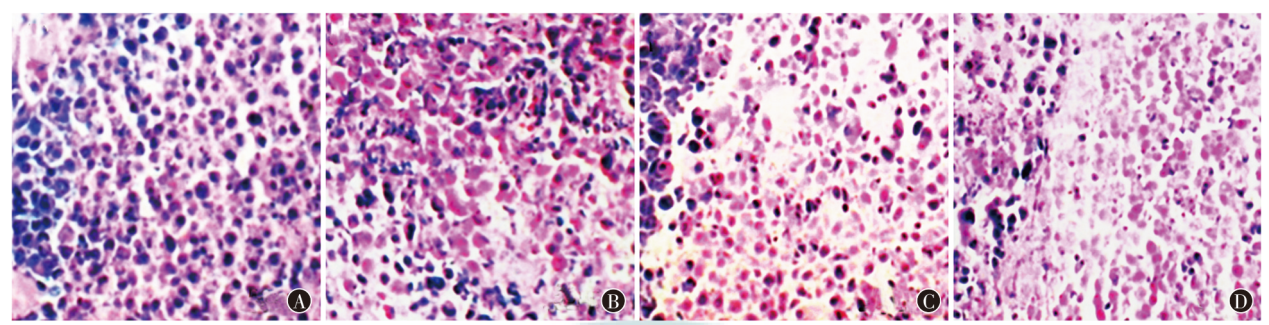

目的 探究雷帕霉素动脉灌注联合负载131I-成纤维细胞活化蛋白(FAP)的葡聚糖微球介入栓塞治疗兔肝移植瘤的效果。方法 选取50只雄性新西兰白兔,采用随机数字表法将40只白兔用于建模肝移植瘤,随机分为阴性对照组(基于动脉灌注同体积生理盐水,MO)组,雷帕霉素动脉灌注(RA)组,负载131I-FAP的葡聚糖微球介入栓塞治疗(IF)组,雷帕霉素动脉灌注联合负载131I-FAP的葡聚糖微球介入栓塞治疗(RI)组,每组10只;余10只未建模白兔为正常(基于动脉灌注同体积生理盐水,NO)组。采用HE染色检测肿瘤细胞病理形态,全自动生化分析仪检测肝功能,TUNEL法检测肿瘤细胞凋亡情况,蛋白质印迹法检测肝组织血管内皮生长因子(VEGF)、血管内皮生长因子受体(VEGFR)蛋白表达情况。结果 MO组、RA组、IF组、RI组肿瘤质量分别为(20.33±2.39)、(14.62±1.23)、(14.34±1.22)、(8.28±0.84)g,肿瘤体积分别为(0.87±0.13)、(0.51±0.09)、(0.53±0.08)、(0.32±0.02)cm3,肿瘤坏死率分别为(21.11±2.14)%、(32.18±3.25)%、(32.29±3.28)%、(48.53±4.37)%,抑瘤率分别为(0.00±0.00)%、(24.66±2.47)%、(24.13±2.46)%、(45.55±4.51)%,差异均有统计学意义(F=316.40,P<0.001;F=159.50,P<0.001;F=356.10,P<0.001;F=571.30,P<0.001);与MO组比较,RA组、IF组、RI组差异均有统计学意义(均P<0.05);IF组与RI组比较,差异均有统计学意义(均P<0.05)。MO组肿瘤细胞呈浸润生长,核分裂像多见,未见明显坏死,可见大量炎性细胞浸润,RA组、IF组、RI组癌巢明显变小,肿瘤细胞出现肿胀、核固缩及大量坏死,炎性细胞浸润明显减轻,其中RI组改善最为明显。NO组、MO组、RA组、IF组、RI组白蛋白(ALB)水平分别为(40.55±4.38)、(17.34±1.02)、(22.65±2.18)、(22.37±2.17)、(29.01±2.83)g/L,丙氨酸氨基转移酶(ALT)水平分别为(19.68±1.34)、(92.17±9.24)、(78.71±7.39)、(78.35±7.40)、(50.30±5.12)U/L,天冬氨酸氨基转移酶(AST)水平分别为(74.27±7.48)、(182.21±20.23)、(165.78±16.05)、(165.26±16.09)、(102.33±11.11)U/L,总胆红素(TBIL)水平分别为(22.42±2.58)、(82.24±8.35)、(61.86±6.17)、(61.53±6.16)、(46.45±4.53)μmoL/L,差异均有统计学意义(F=105.90,P<0.001;F=189.00,P<0.001;F=99.57,P<0.001;F=142.10,P<0.001);与NO组比较,MO组、RA组、IF组、RI组差异均有统计学意义(均P<0.05);与MO组比较,RA组、IF组、RI组差异均有统计学意义(均P<0.05);IF组与RI组比较,差异均有统计学意义(均P<0.05)。MO组、RA组、IF组、RI组肿瘤细胞凋亡率分别为(9.01±1.23)%、(15.65±1.68)%、(15.72±1.69)%、(24.34±2.12)%,差异有统计学意义(F=135.30,P<0.001);与MO组比较,RA组、IF组、RI组差异均有统计学意义(均P<0.05);IF组与RI组比较,差异有统计学意义(P<0.05)。NO组、MO组、RA组、IF组、RI组VEGF表达水平分别为1.33±0.13、2.28±0.21、1.88±0.19、1.86±0.18、1.50±0.14,VEGFR表达水平分别为1.32±0.09、2.14±0.28、1.91±0.18、1.89±0.17、1.62±0.15,差异均有统计学意义(F=45.84,P<0.001;F=29.05,P<0.001);与NO组比较,MO组、RA组、IF组、RI组差异均有统计学意义(均P<0.05);与MO组比较,RA组、IF组、RI组差异均有统计学意义(均P<0.05);IF组与RI组比较,差异均有统计学意义(均P<0.05)。结论 雷帕霉素动脉灌注联合负载131I-FAP的葡聚糖微球介入栓塞治疗兔肝移植瘤,可有效抑制肿瘤生长,提高肿瘤坏死率、抑瘤率以及凋亡能力,改善肝功能指标,对兔肝移植瘤有显著疗效。

Objective To investigate the efficacy of rapamycin arterial perfusion combined with 131I-fibroblast activation protein (FAP) loaded dextran microspheres in the treatment of rabbits with liver transplantation tumor. Methods Fifty male New Zealand white rabbits were selected. Forty white rabbits were used to establish liver transplantation tumor models and were randomly divided into a negative control (based on arterial perfusion with the same volume of normal saline, MO) group, rapamycin arterial perfusion (RA) group, 131I-FAP loaded dextran microspheres for interventional embolization therapy (IF) group, and rapamycin arterial perfusion combined with 131I-FAP-loaded dextran microspheres interventional embolization therapy (RI) group by the random number table method, with 10 rabbits in each group. The remaining 10 unmodeled white rabbits were classified as the normal (based on arterial perfusion with the same volume of normal saline, NO) group. The pathological morphology of tumor tissues was detected by HE staining, liver function was detected by automatic biochemical analyzer, apoptosis of tumor cells was detected by TUNEL method, and the protein expression of vascular endothelial growth factor (VEGF) and vascular endothelial growth factor receptor (VEGFR) in liver tissues was detected by Western blotting. Results The tumor mass of MO group, RA group, IF group and RI group was (20.33±2.39), (14.62±1.23), (14.34±1.22), (8.28±0.84) g, respectively. Tumor volumes were (0.87±0.13), (0.51±0.09), (0.53±0.08), (0.32±0.02) cm3, respectively. Tumor necrosis rates were (21.11±2.14)%, (32.18±3.25)%, (32.29±3.28)%, (48.53±4.37)%, respectively. Tumor suppression rates were (0.00±0.00)%, (24.66±2.47)%, (24.13±2.46)%, (45.55±4.51)%, respectively. There were statistically significant differences (F=316.40, P<0.001; F=159.50, P<0.001; F=356.10, P<0.001; F=571.30, P<0.001); there were statistically significant differences in RA, IF and RI groups compared with the MO group (all P<0.05); there were statistically significant differences between RI group and IF group (all P<0.05). Tumor cells of MO group showed infiltrating growth, with more mitotic images, no obvious necrosis, and a large number of inflammatory cell infiltration. Cancer nests in RA group, IF group and RI group became significantly smaller, tumor cells showed swelling, nuclear contraction and a large number of necrosis, and inflammatory cell infiltration was significantly reduced, among which the improvement was most obvious in RI group. The albumin (ALB) level of NO group, MO group, RA group, IF group and RI group was (40.55±4.38), (17.34±1.02), (22.65±2.18), (22.37±2.17), (29.01±2.83) g/L, respectively. The alanine aminotransferase (ALT) level was (19.68±1.34), (92.17±9.24), (78.71±7.39), (78.35±7.40), (50.30±5.12) U/L, respectively. The aspartate aminotransferase (AST) level was (74.27±7.48), (182.21±20.23), (165.78±16.05), (165.26±16.09), (102.33±11.11) U/L, respectively. The total bilirubin (TBIL) level was (22.42±2.58), (82.24±8.35), (61.86±6.17), (61.53±6.16), (46.45±4.53) μmoL/L, respectively. There were statistically significant differences (F=105.90, P<0.001; F=189.00, P<0.001; F=99.57, P<0.001; F=142.10, P<0.001); there were statistically significant differences in MO, RA, IF, RI groups compared with the NO group (all P<0.05); there were statistically significant differences in RA, IF, RI groups compared with the MO group (all P<0.05); there were statistically significant differences between IF group and RI group (all P<0.05). The apoptosis rates in MO group, RA group, IF group and RI group were (9.01±1.23)%, (15.65±1.68)%, (15.72±1.69)% and (24.34±2.12)%, respectively, and there was a statistically significant difference (F=135.30, P<0.001); there were statistically significant differences in RA, IF and RI groups compared with the MO group (all P<0.05); there was a statistically significant difference between RI group and IF group (P<0.05). VEGF expression level in NO group, MO group, RA group, IF group and RI group was 1.33±0.13, 2.28±0.21, 1.88±0.19, 1.86±0.18 and 1.50±0.14, respectively. VEGFR expression level was 1.32±0.09, 2.14±0.28, 1.91±0.18, 1.89±0.17, 1.62±0.15, respectively. There were statistically significant differences (F=45.84, P<0.001; F=29.05, P<0.001); there were statistically significant differences in MO, RA, IF, RI groups compared with the NO group (all P<0.05); there were statistically significant differences in RA, IF, RI groups compared with the MO group (all P<0.05); there were statistically significant differences between IF group and RI group (both P<0.05). Conclusions Rapamycin arterial perfusion combined with 131I-FAP-loaded dextran microspheres interventional embolization therapy in the treatment of rabbits with liver transplantation tumor can effectively inhibit tumor growth, enhance the tumor necrosis rate, tumor inhibition rate and apoptotic ability, improve liver function indicators, and has a significant therapeutic effect on rabbits with liver transplantation tumor.